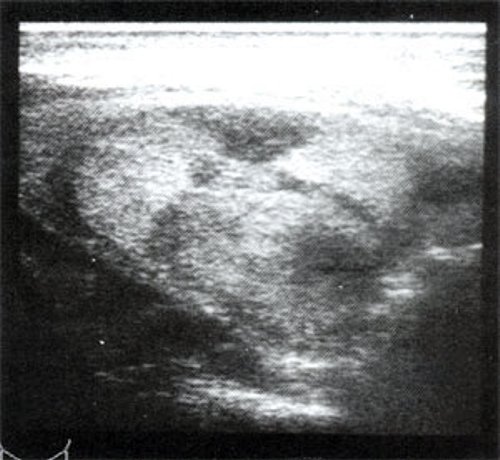

Тиреоидит. Диффузно увеличенная железа, может быть асимметричной с гипоэхогенной структурой (100%) и содержать отдельные узлы (рис. 6).

Рис. 6. Варианты тиреоидита.